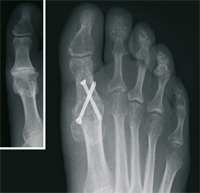

Nach ausführlicher Untersuchung, Betrachtung der individuellen Erfordernisse, sowie Analyse der Röntgenbilder wird die Behandlung festgelegt. Hierbei kommen verschiedene international anerkannte Operationsverfahren zur Anwendung. Wir verwenden dabei modernste Platten und Schrauben aus Titan.

Krallenzehe

Die Krallenzehe oder Hammerzehe beschreibt eine Fehlstellung bzw. Verkrümmung der Kleinzehen. Durch zunehmende Verkürzung zunächst der Beugesehne im Mittelgelenk, dann der Strecksehne im Grundgelenk, kommt es zu einer Verkrümmung der Zehe. Hierdurch entstehen Schmerzen und Verhornungen unter dem Vorfußballen, sowie schmerzhafte Druckstellen über den Mittelgelenken (Hühneraugen). Diese Fehlstellung lässt sich meistens nur operativ korrigieren. Durch eine Verlängerung der Strecksehne und Lösung der Gelenkkapsel, verbunden mit einer Versteifung im Zehenmittelgelenk, wird die Zehe dauerhaft begradigt. Die Druckstellen und Schmerzen gehen zurück.